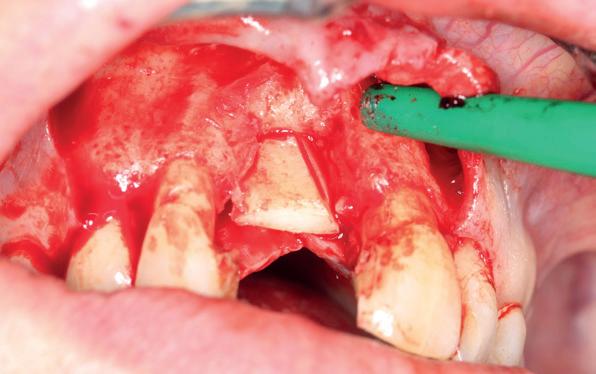

Uitvoering restauratieve fase

In het onderfront werd autoloog bot geoogst uit de kin regio ten behoeve van augmentatie (afbeelding

9. Botopbouw onderfront

9). In de bovenkaak werd bilateraal een sinuslift uitgevoerd. Aansluitend werden in beide kaakhelften implantaten geplaatst (afbeelding 10).